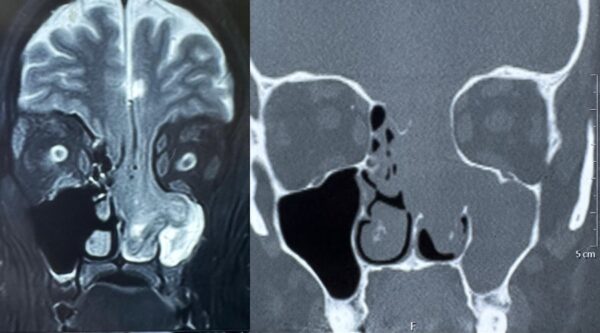

In a rare medical case, doctors at HCMCT Manipal Hospital Dwarka, Delhi, successfully treated a 33-year-old woman suffering from a severe condition in which a portion of her brain had herniated through the skull base into the nasal cavity and sinuses. The brain tissue had descended into her nasal passage and oral cavity due to erosion of […]